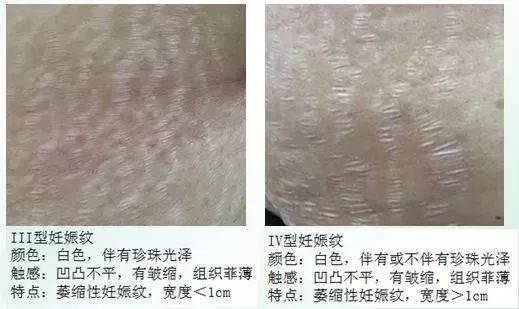

怀孕期间的妊娠纹,

在妊娠期荷尔蒙作用下往往呈现粉色或深紫色

在产后几个月到几年时间内,

色素部分会慢慢消退,

留下白色或银白色的有光泽的瘢痕。

色素还算好解决,

会自己慢慢代谢掉,

或者采用一些医美手段淡化。

但是瘢痕就很难办了,

一旦形成是不会消失的。

不仅视觉上看起来有褶皱感,

摸起来也有凹凸不平的触感。

妊娠纹这东西主要看基因,先天因素占主导。后天我们能够抓住的变量相当有限。而且妊娠纹并不仅仅在表皮层,它不是简单的“纹路”,而是“撕裂”!所以妊娠纹的英文叫做stretch marks,这样表达更为准确。它的形成是由于皮下组织,肌肉/脂肪等过度拉伸,导致了皮肤纤维断裂。深度比我们平时常见的皱纹,疤痕等要深得多。而且皮肤纤维一旦断裂就是不可逆的,无法恢复原有平整的外观。任何宣传对妊娠纹有效的产品,医美手段,最多只能做到“改善”,让妊娠纹看起来不那么明显。但要100%完全去除,目前无论外用护肤品,还是医美仪器都没有一个有效的方法手段。

妊娠纹是萎缩纹的一种。萎缩纹是人体在怀孕、健身、体重骤增过程当中产生的皮肤纤维断裂现象,呈红色、白色或紫色条纹。它还包括肥胖纹、运动裂纹等。很多人在发育过程中,由于身高/体重增长过快,也会形成类似的生长纹。